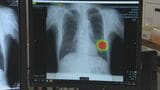

肺がん検診など胸部X線診断に「AI」導入 検診分野では中四国初